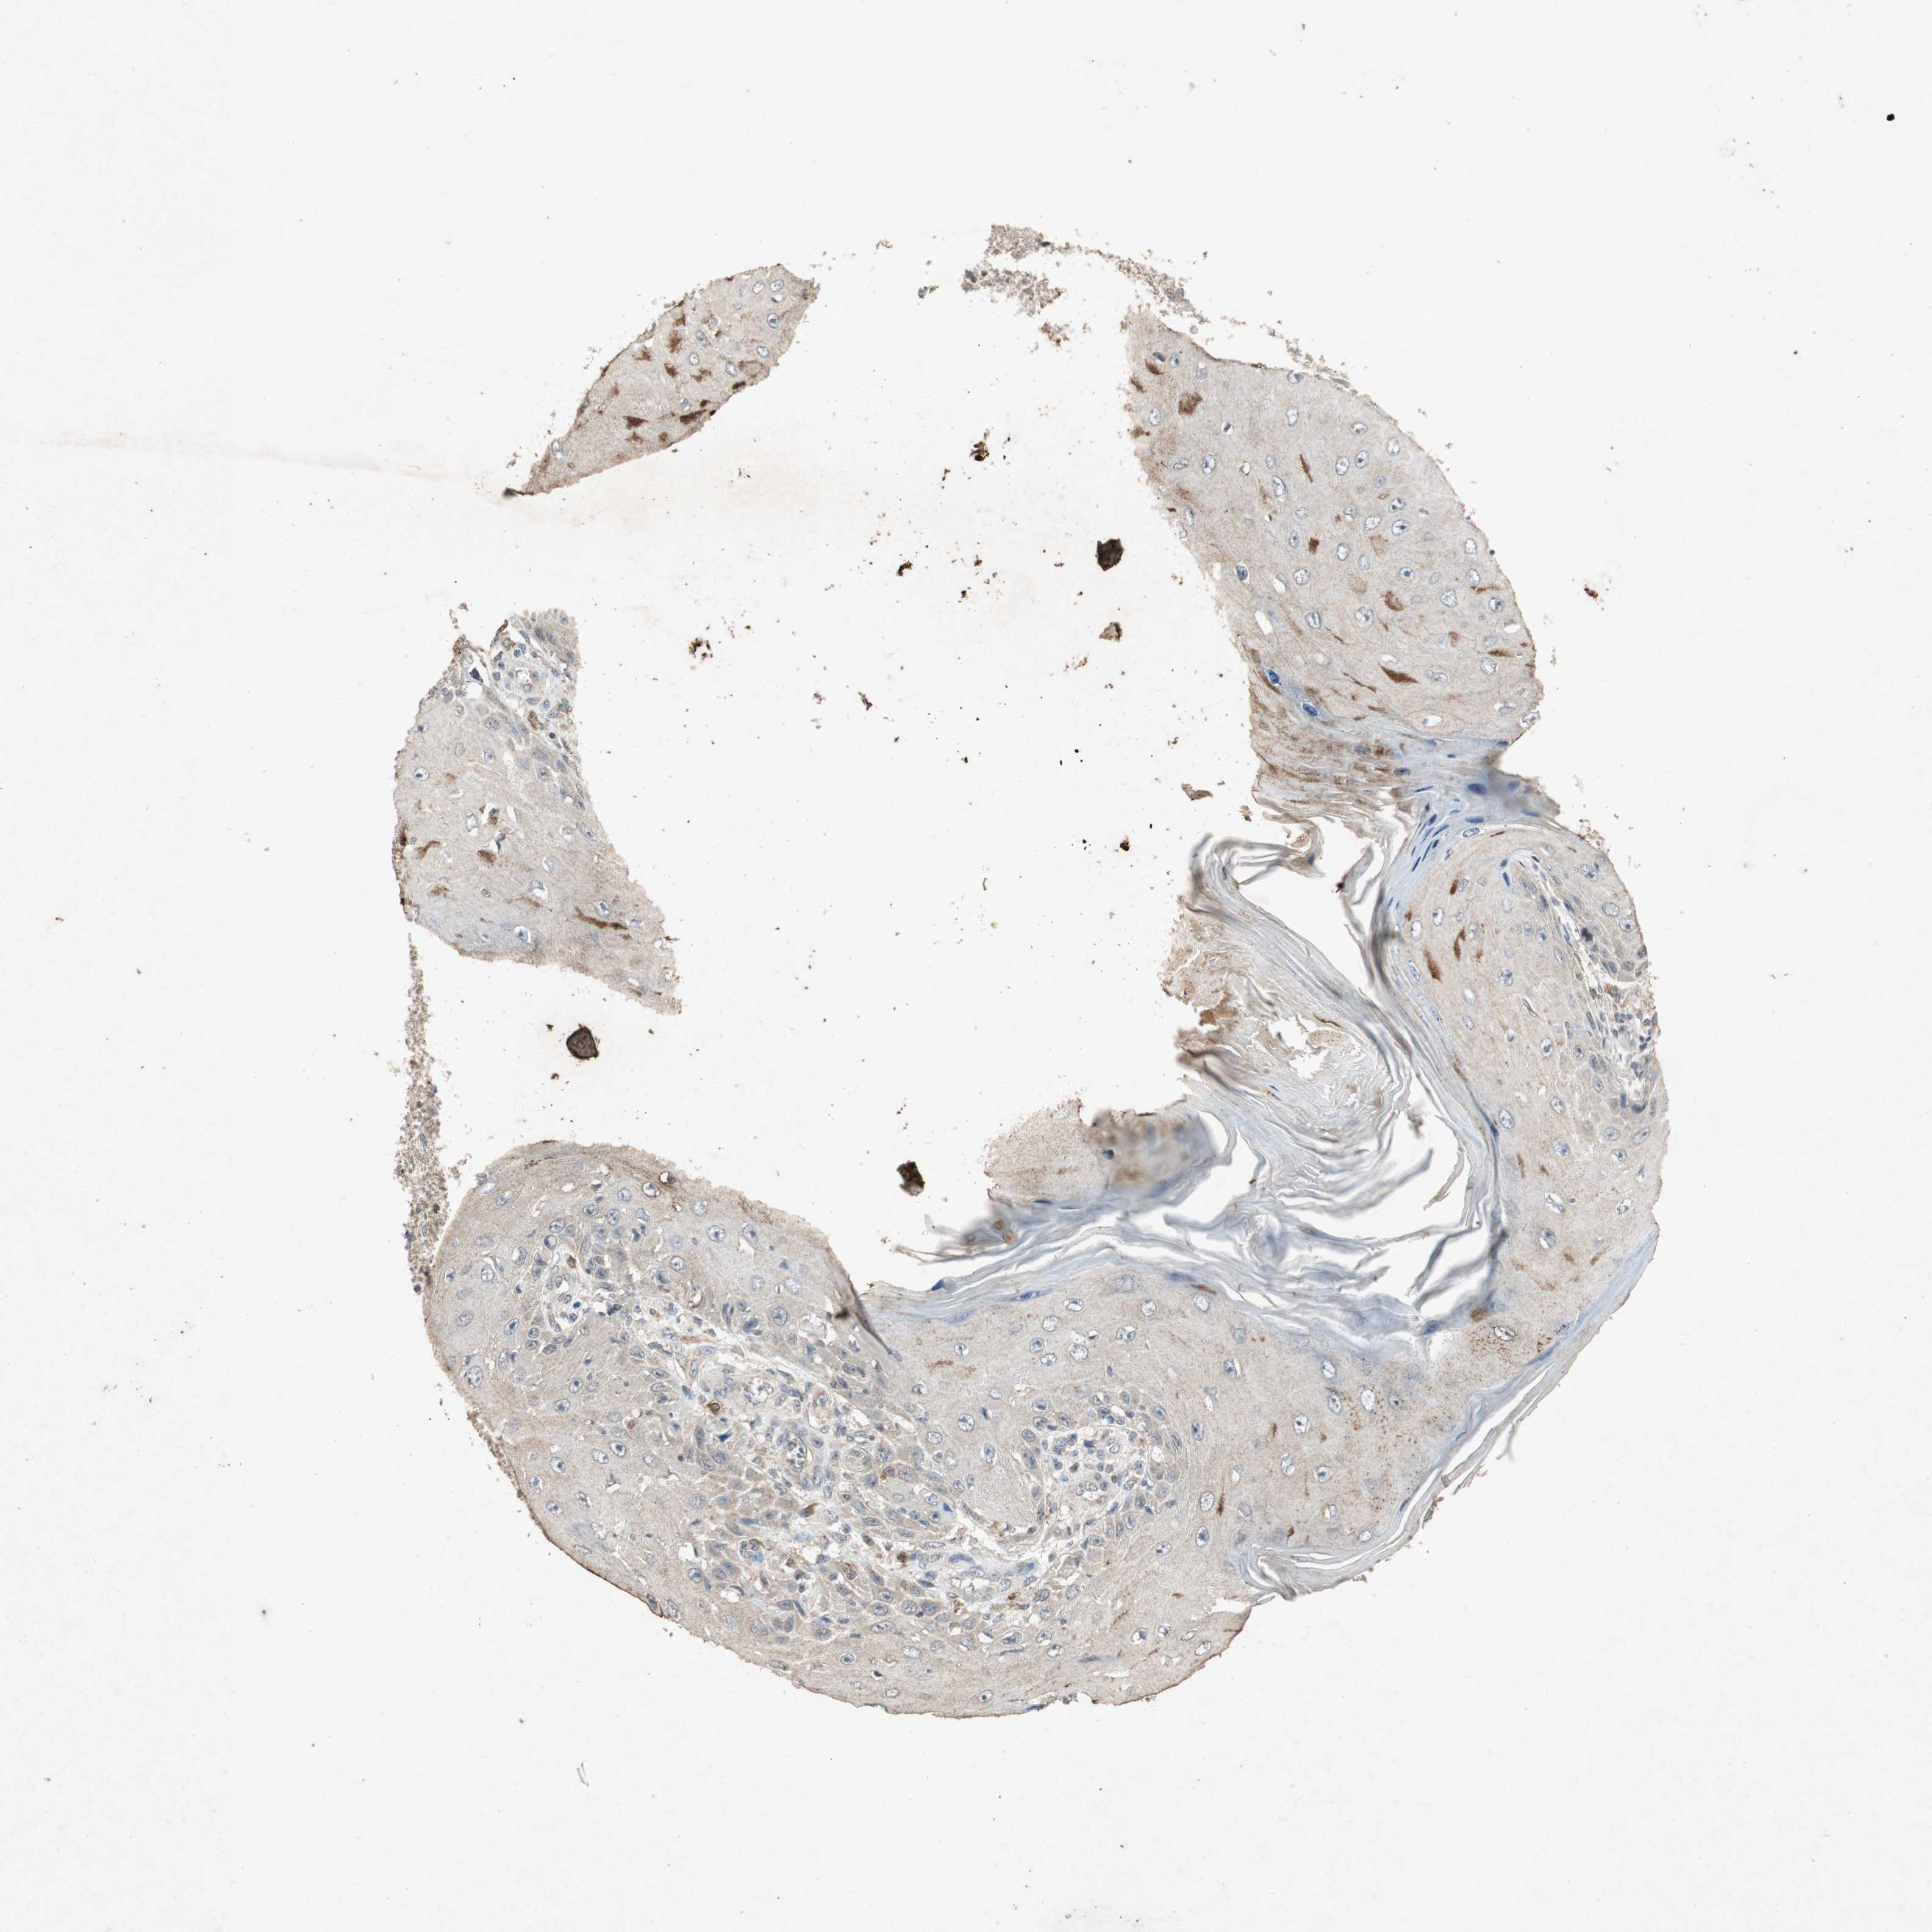

SKIN CANCER - Protein expressioni

A mouse-over function shows sample information and annotation data. Click on an image to view it in a full screen mode. Samples can be filtered based on level of antibody staining by selecting one or several of the following categories: high, medium, low and not detected. The assay and annotation is described here.

Antibody stainingi

Antibody staining in the annotated cell types in the current human tissue is reported as not detected, low, medium, or high, based on conventional immunohistochemistry profiling in selected tissues. This score is based on the combination of the staining intensity and fraction of stained cells.

Each image is clickable and will lead to virtual microscopy that enables deeper exploration of all samples and also displays staining intensity scores, fraction scores and subcellular localization as well as patient and tissue information for each sample.

Basal cell carcinoma

Squamous cell carcinoma, NOS